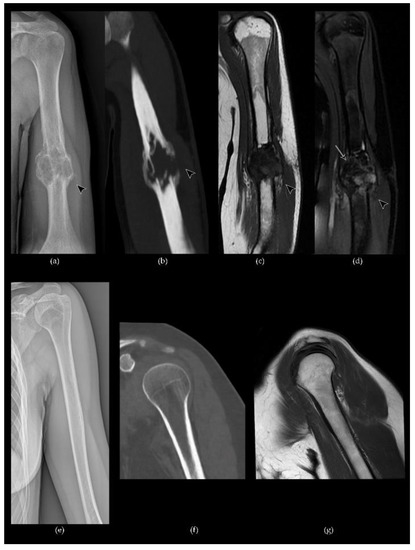

- Murphey, M.D.; Nomikos, G.C.; Flemming, D.J.; Gannon, F.H.; Temple, H.T.; Kransdorf, M.J. From the archives of the AFIP. Imaging of giant cell tumor and giant cell reparative granuloma of bone: Radiologie-pathologic correlation. Radiographics 2001, 21, 1283–1309. [Google Scholar] [CrossRef] [PubMed]

- Chakarun, C.J.; Forrester, D.M.; Gottsegen, C.J.; Patel, D.B.; White, E.A.; Matcuk, G.R. Giant cell tumor of bone: Review, mimics, and new developments in treatment. Radiographics 2013, 33, 197–211. [Google Scholar] [CrossRef]

- Baumgartner, K.; Haap, M.; Bösmüller, H.; Horger, M. Imaging of giant cell tumors of the bone, RoFo Fortschritte Auf Dem Gebiet Der Rontgenstrahlen Und Der Bildgeb. Verfahren 2020, 193. [Google Scholar] [CrossRef]

- Xu, L.; Jin, J.; Hu, A.; Xiong, J.; Wang, D.; Sun, Q.; Wang, S. Soft tissue recurrence of giant cell tumor of the bone: Prevalence and radiographic features. J. Bone Oncol. 2017, 9, 10–14. [Google Scholar] [CrossRef]

- Wang, C.S.; Lou, J.H.; Liao, J.S.; Ding, X.Y.; Du, L.J.; Lu, Y.; Yan, L.; Chen, K.M. Tumore osseo a cellule giganti recidivante: Caratteristiche radiologiche e fattori di rischio. Radiol. Med. 2013, 118, 456–464. [Google Scholar] [CrossRef]

- Costelloe, C.M.; Kumar, R.; Yasko, A.W.; Murphy, W.A.; Stafford, R.J.; Lewis, V.O.; Lin, P.P.; Madewell, J.E. Imaging characteristics of locally recurrent tumors of bone. Am. J. Roentgenol. 2007, 188, 855–863. [Google Scholar] [CrossRef] [PubMed]

- Park, S.Y.; Lee, M.H.; Lee, J.S.; Song, J.S.; Chung, H.W. Ossified soft tissue recurrence of giant cell tumor of the bone: Four case reports with follow-up radiographs, CT, ultrasound, and MR images. Skelet. Radiol. 2014, 43, 1457–1463. [Google Scholar] [CrossRef]